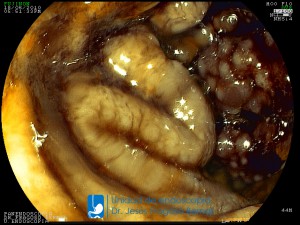

La Unidad de Endoscopía fue creada en 2002 por el Dr. Jesús Fragoso Bernal, es pionera en el estado por la utilización de la tecnología más avanzada, que nos permite ofrecer servicios integrales de diagnóstico y tratamiento para las enfermedades del aparato digestivo.